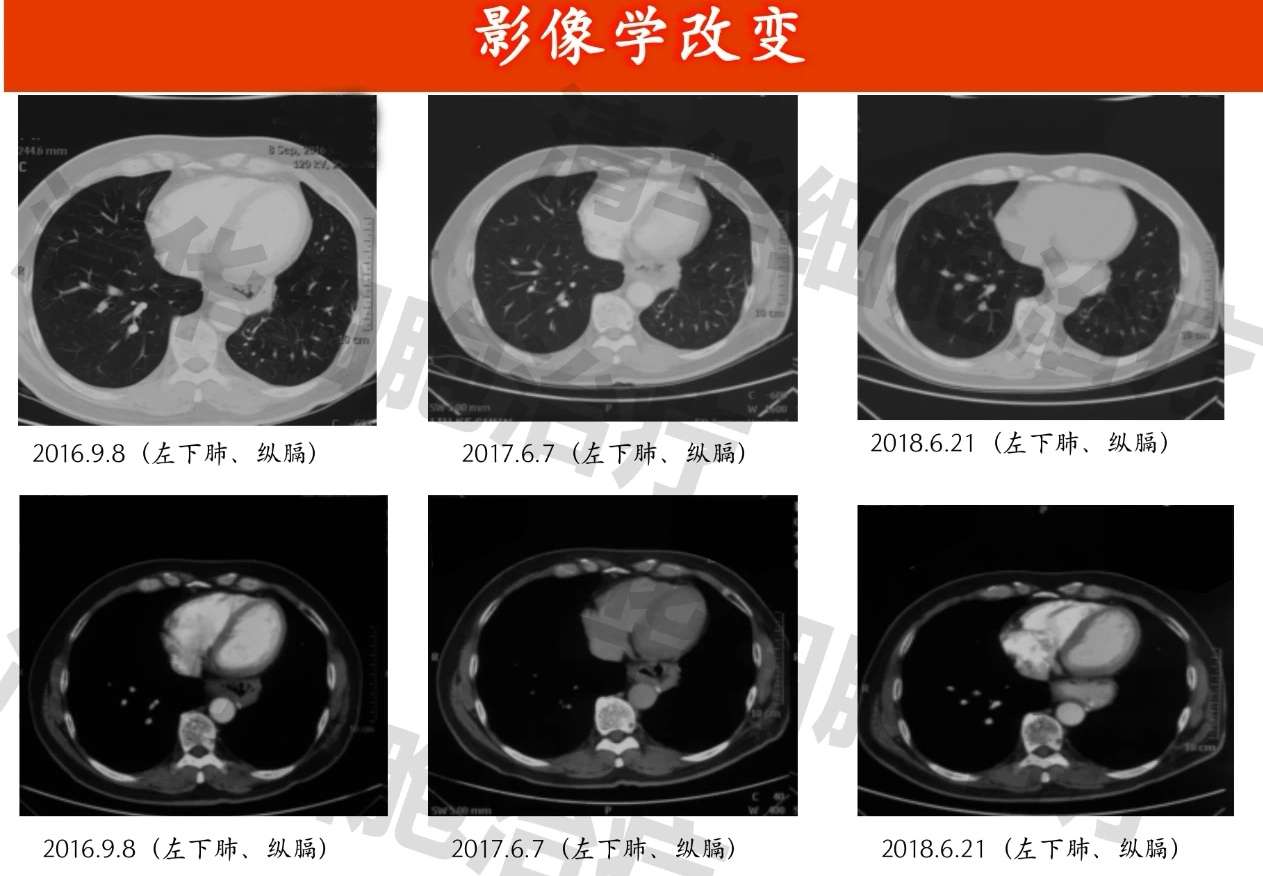

03.影像资料:

贲门癌术后改变,2014年2月表现为胃吻合口显示不均匀增厚,周围边界不清,左侧胸腔少量积液,考虑手术引起,后2014年11月至2020年7月多次复查胃吻合口壁未见明显增厚,胸腔积液吸收。术区未见局部复发征象。